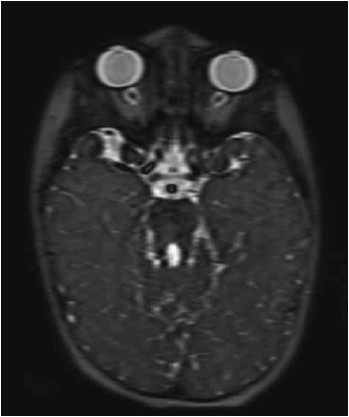

Paciente do sexo feminino, 2 anos, com atraso no desenvolvimento, ataxia e apraxia oculomotora. Realizou a ressonância magnética de crânio mostrada a seguir.

Nesse caso, o diagnóstico é: